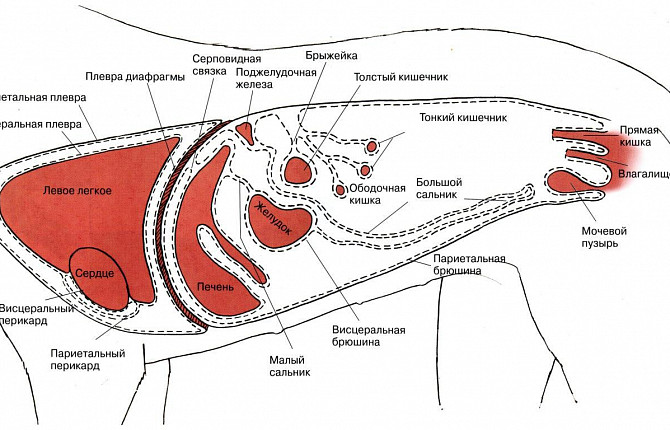

Плевральная полость - это щелевидное пространство между висцеральным и париетальным листками плевры, окружающими каждое легкое. Плевра представляет собой гладкую серозную оболочку. Париетальный или наружный листок плевры выстилают стенки грудной полости и наружные поверхности средостения, покрывают лёгкое и его анатомические структуры (сосуды, бронхи и нервы). В норме плевральные полости содержат незначительное количество серозной жидкости.